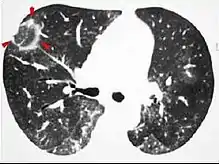

CT scan showing cryptogenic organizing pneumonia (biopsy-proven)

The reversed halo sign is seen in about 20% of individuals with COP.[18]

The chest x-ray is distinctive with features that appear similar to an extensive pneumonia, with both lungs showing widespread white patches. The white patches may seem to migrate from one area of the lung to another as the disease persists or progresses. Computed tomography (CT) may be used to confirm the diagnosis. Often the findings are typical enough to allow the doctor to make a diagnosis without ordering additional tests.[19] To confirm the diagnosis, a doctor may perform a lung biopsy using a bronchoscope. Many times, a larger specimen is needed and must be removed surgically.

Plain chest radiography shows normal lung volumes, with characteristic patchy unilateral or bilateral consolidation. Small nodular opacities occur in up to 50% of patients and large nodules in 15%. On high resolution computed tomography, airspace consolidation with air bronchograms is present in more than 90% of patients, often with a lower zone predominance. A subpleural or peribronchiolar distribution is noted in up to 50% of patients. Ground glass appearance or hazy opacities associated with the consolidation are detected in most patients.

While patchy bilateral disease is typical, there are unusual variants of organizing pneumonia where it may appear as multiple nodules or masses. One rare presentation, focal organizing pneumonia, may be indistinguishable from lung cancer based on imaging alone, requiring biopsy or surgical resection to make the diagnosis.[20]